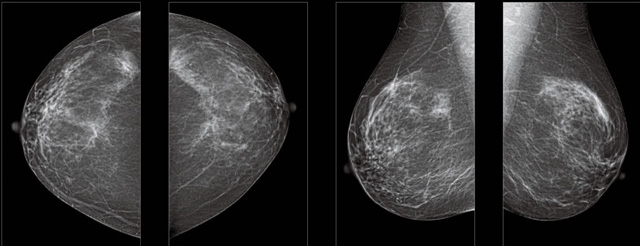

首先不同年龄阶段的乳腺筛查频次种类不一样。青春期女性第二性征明显发育开始,每个月进行自我乳腺检查。20-30岁的女性就不推荐进行乳腺检查,因为年轻女性的乳腺组织非常紧急。钼靶X光线等检查的射线不能辨别肿块跟腺体。身体就白吸收了辐射,影响了身体健康。每个月自检一次就是在洗澡时候,对着镜子看看乳房外观正常,皮肤溃烂、肿块、颜色改变、再摸一下有没小疙瘩。乳腺高危人群,特别是有乳腺CA遗传倾向的女性,乳腺导管跟小叶不典型增生,原位癌。30岁前有乳房放疗的女性。乳腺癌筛查可以把年龄提前到40岁前。40到70岁的女性可以在适合的机会筛查。

采用影像检查技术来发现疑似特定病检查跟人群的普查。一到两年进行一次X光线的乳腺检查。记过是C或者D型,可以加上B超协同。还可以一年一次核磁共振MRI检查。70岁以上的女性认为绝经的女性是比较安全的。实际上也有乳腺癌的风险。65岁以上风险也很大。也是需要进行机会性筛查。